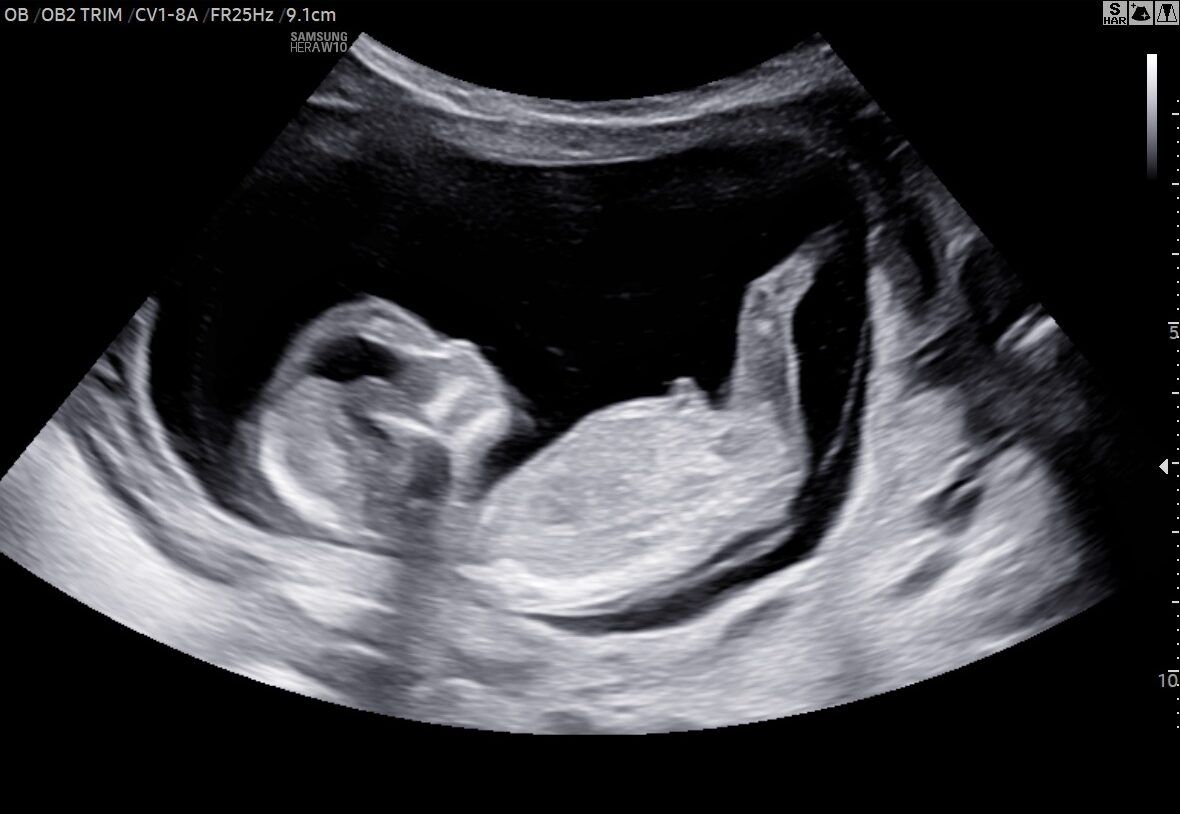

Ønsker I at se, hvordan jeres barn har det, og om det vokser, som det skal? Så kan I få lavet en tryghedsscanning her hos Den lille Jordemoder. Her ser vi på, hvordan barnet har det nede i livmoderen, og vi laver en vækstberegning, så I kan få et indblik i, hvordan barnet vokser. Derudover vurderer vi barnets placering og lytter til hjertelyden.

Det er naturligvis en fantastisk og spændende tid at gå igennem en graviditet. For mange byder graviditeten dog også på bekymringer og frygt om, hvorvidt barnet nu også vokser, som det burde, og generelt har det godt. Netop derfor tilbyder vi tryghedsscanninger, der også kaldes trivselsscanninger. Med denne scanning kan I slippe bekymringerne og vide jer sikre på, at jeres lille barn har det godt.

Ved en tryghedsscanning får I både printede billeder, en vækstrapport, optagelser af barnets hjertelyd og billeder overført til telefonen med hjem, som I kan kigge på efterfølgende.